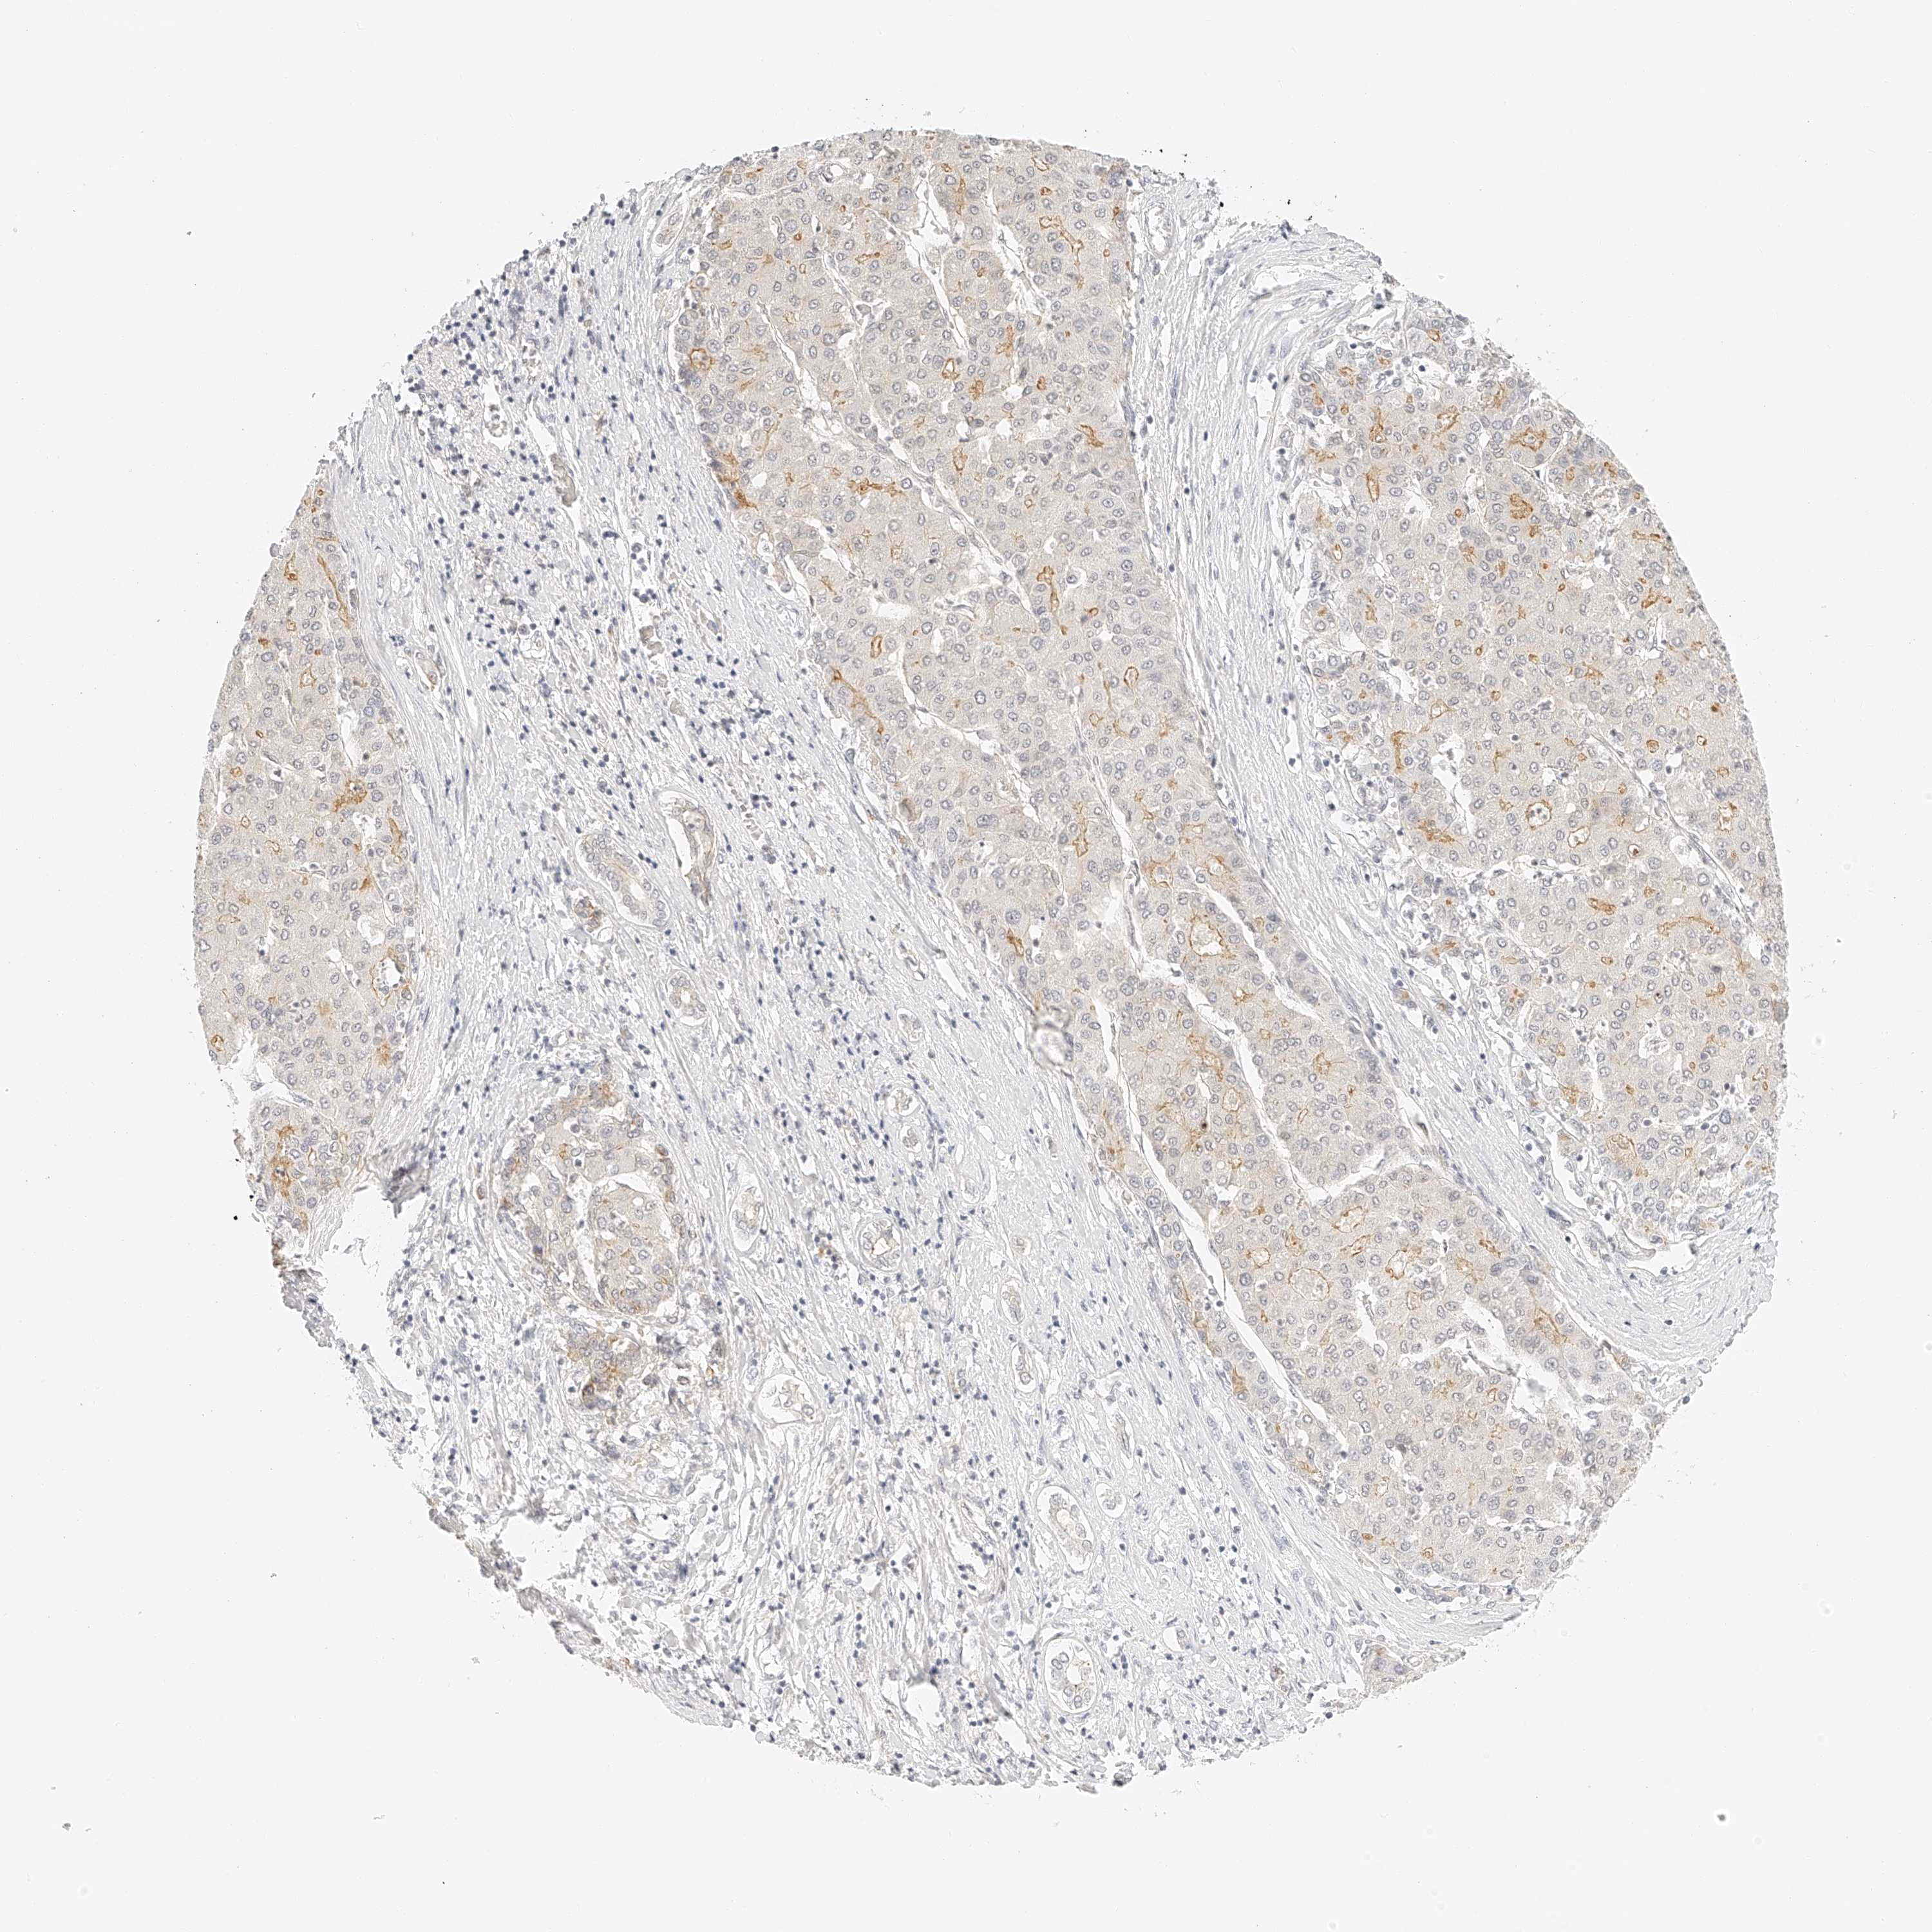

LIVER CANCER - Protein expressioni

A mouse-over function shows sample information and annotation data. Click on an image to view it in a full screen mode. Samples can be filtered based on level of antibody staining by selecting one or several of the following categories: high, medium, low and not detected. The assay and annotation is described here.

Note that samples used for immunohistochemistry by the Human Protein Atlas do not correspond to samples in the TCGA dataset.

Antibody stainingi

Antibody staining in the annotated cell types in the current human tissue is reported as not detected, low, medium, or high, based on conventional immunohistochemistry profiling in selected tissues. This score is based on the combination of the staining intensity and fraction of stained cells.

Each image is clickable and will lead to virtual microscopy that enables deeper exploration of all samples and also displays staining intensity scores, fraction scores and subcellular localization as well as patient and tissue information for each sample.

Antibody HPA027808

Staining

High

Medium

Low

Not detected

Intensity

Strong

Moderate

Weak

Negative

Quantity

>75%

75%-25%

<25%

None

Location

Nuclear

Cytoplasmic/membranous

Cytoplasmic/membranous,nuclear

Cholangiocarcinoma

Carcinoma, Hepatocellular, NOS